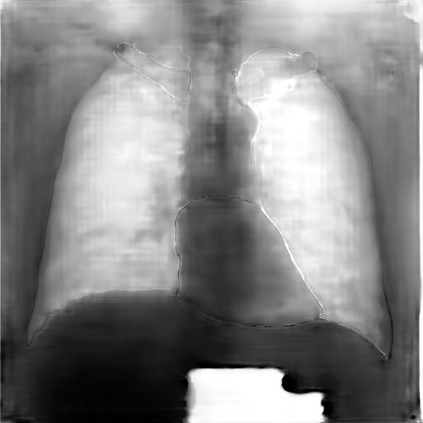

Multi-organ segmentation of X-ray images is of fundamental importance for computer aided diagnosis systems. However, the most advanced semantic segmentation methods rely on deep learning and require a huge amount of labeled images, which are rarely available due to both the high cost of human resources and the time required for labeling. In this paper, we present a novel multi-stage generation algorithm based on Generative Adversarial Networks (GANs) that can produce synthetic images along with their semantic labels and can be used for data augmentation. The main feature of the method is that, unlike other approaches, generation occurs in several stages, which simplifies the procedure and allows it to be used on very small datasets. The method has been evaluated on the segmentation of chest radiographic images, showing promising results. The multistage approach achieves state-of-the-art and, when very few images are used to train the GANs, outperforms the corresponding single-stage approach.